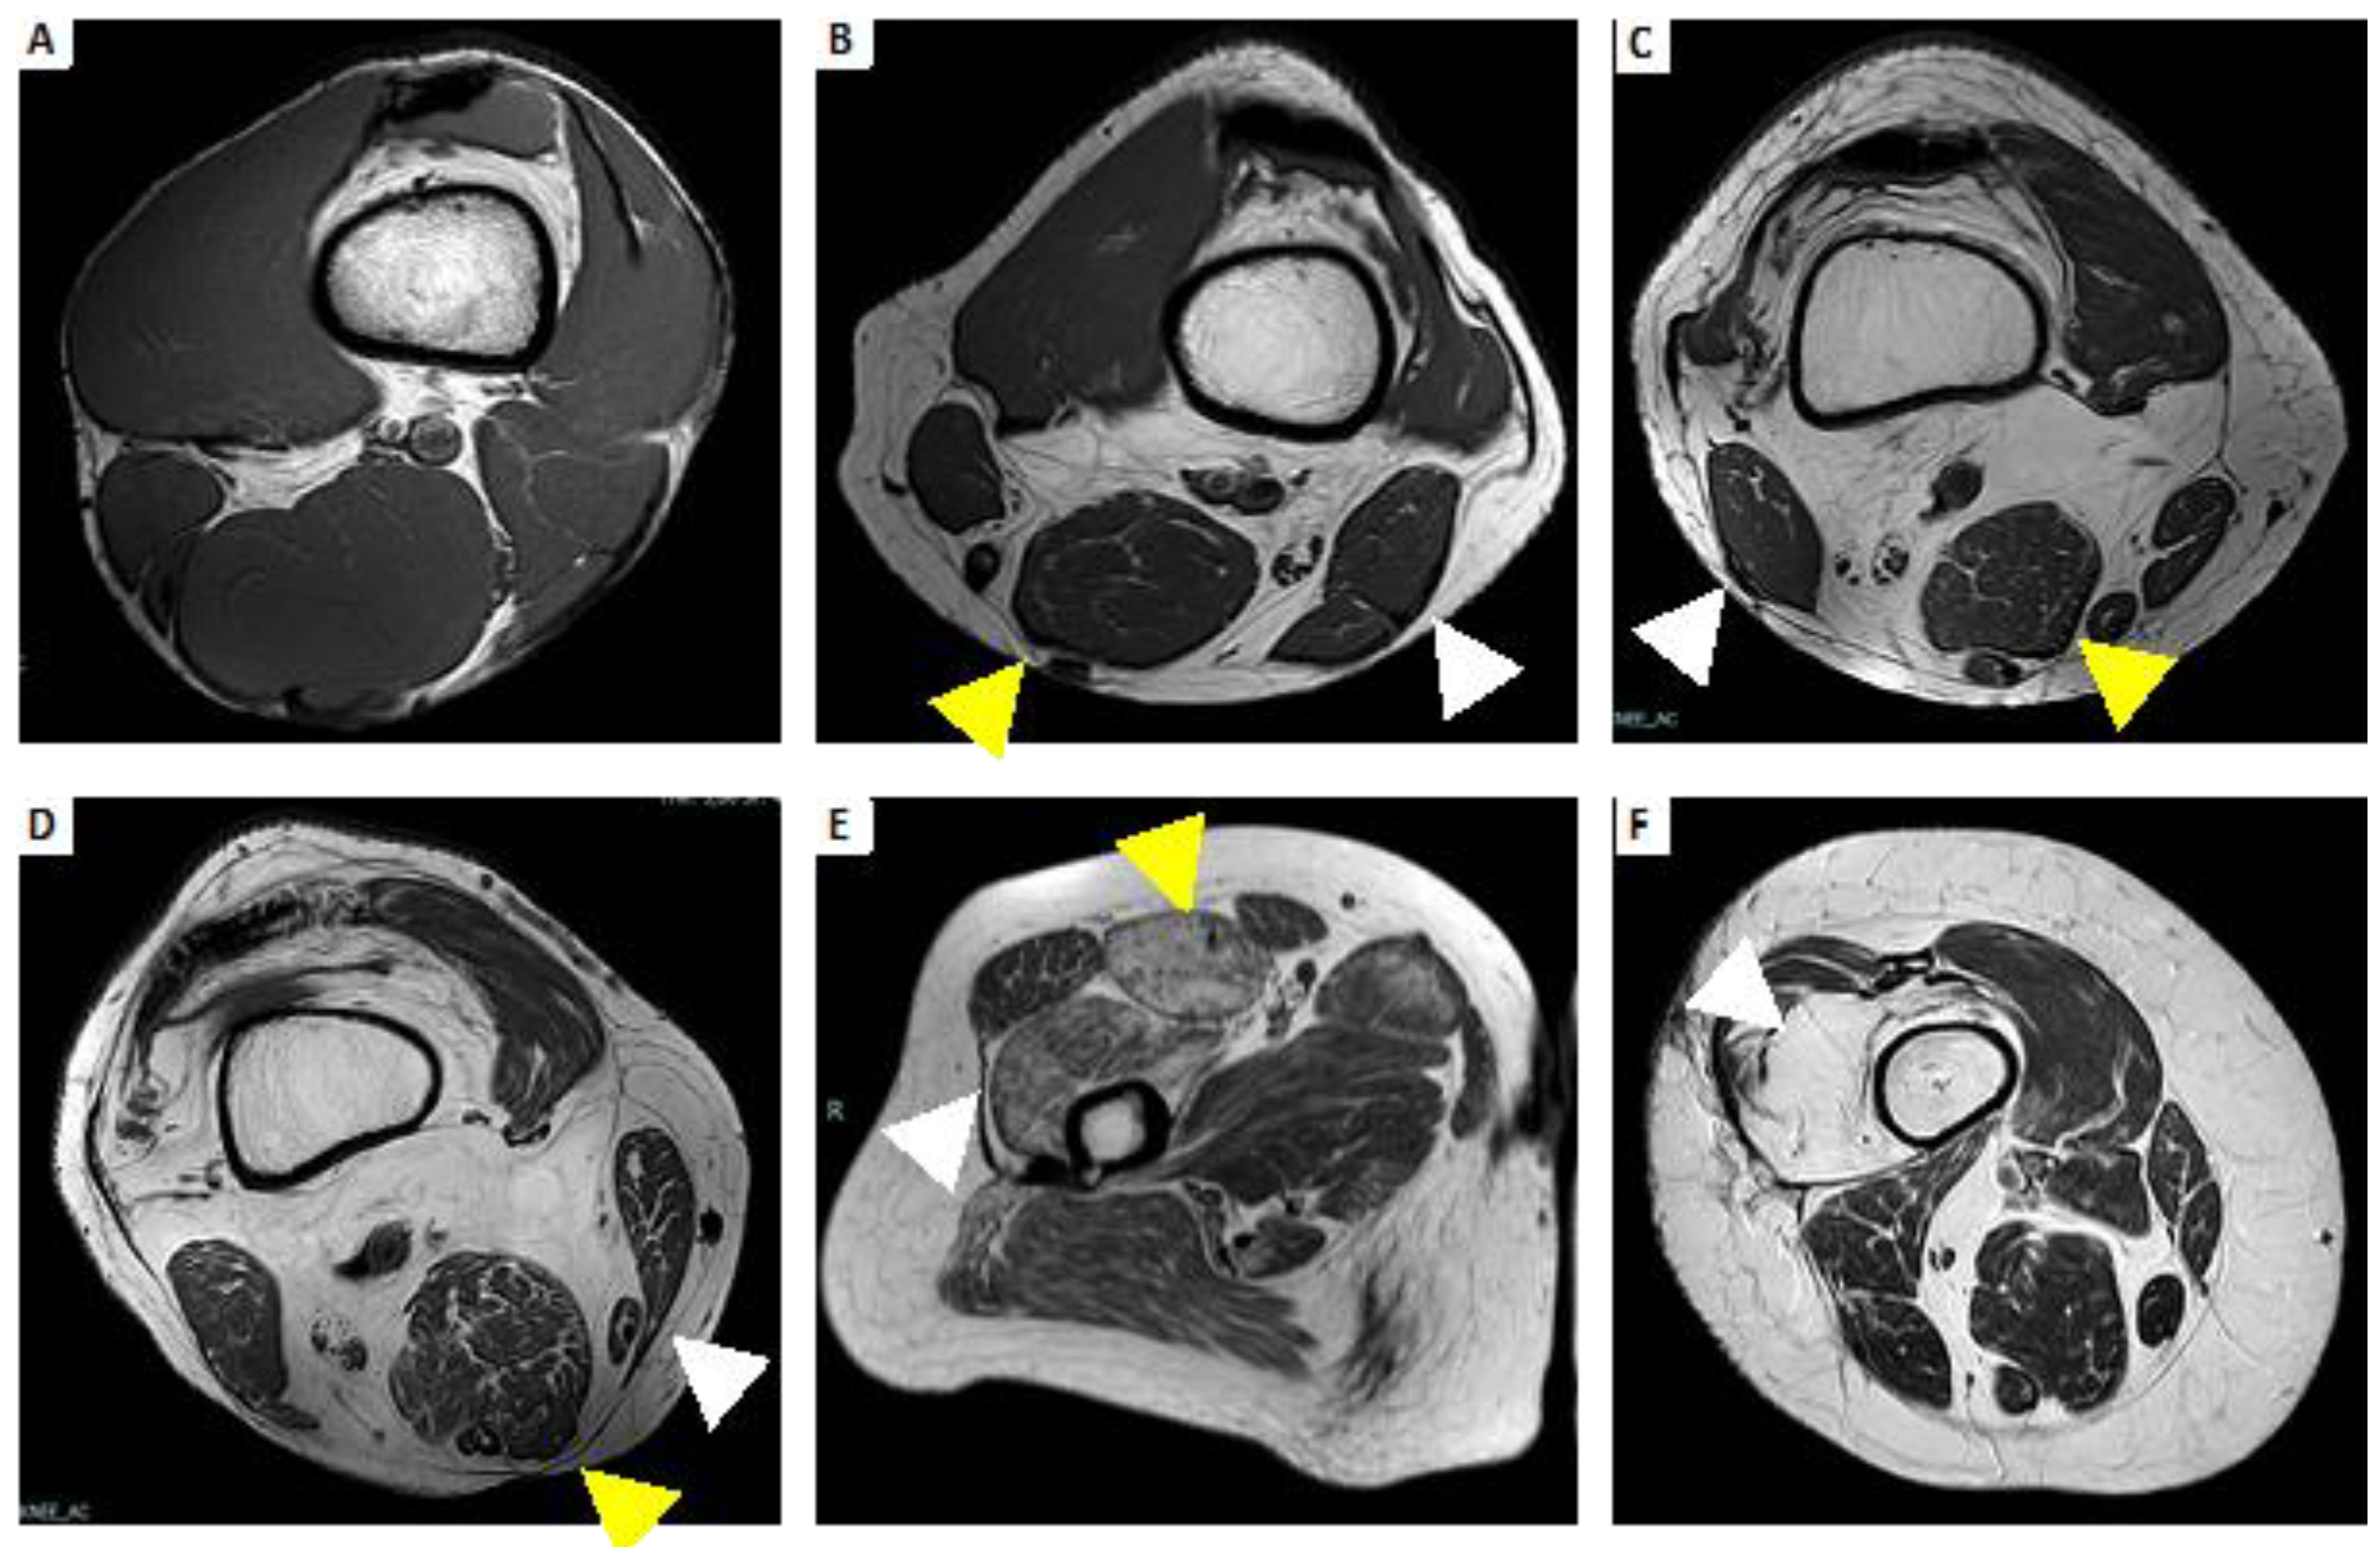

- Spalkit, S.; Sinha, A.; Prakash, M.; Sandhu, M.S. Dermatomyositis: Patterns of MRI findings in muscles, fascia and skin of pelvis and thigh. Eur. J. Radiol. 2021, 141, 109812. [Google Scholar] [CrossRef] [PubMed]

- Karino, K.; Kono, M.; Sakamoto, K.; Fujieda, Y.; Kato, M.; Amengual, O.; Oku, K.; Yasuda, S.; Atsumi, T. Myofascia-dominant involvement on whole-body MRI as a risk factor for rapidly progressive interstitial lung disease in dermatomyositis. Rheumatology 2020, 59, 1734–1742. [Google Scholar] [CrossRef]

- Cantwell, C.; Ryan, M.; O’Connell, M.; Cunningham, P.; Brennan, D.; Costigan, D.; Lynch, T.; Eustace, S. A comparison of inflammatory myopathies at whole-body turbo STIR MRI. Clin. Radiol. 2005, 60, 261–267. [Google Scholar] [CrossRef]

- Del Grande, F.; Carrino, J.A.; Del Grande, M.; Mammen, A.L.; Stine, L.C. Magnetic Resonance Imaging of Inflammatory Myopathies. Top. Magn. Reson. Imaging 2011, 22, 39–43. [Google Scholar] [CrossRef]

| SIDE INVOLVEMENT  | Symmetric | Symmetric | Asymmetric |

| MUSCLE GRADIENT  | Proximal predominance | Proximal predominance | Distal predominance |

| PATTERN OF EDEMA  | Diffuse homogeneous | Peripheral distribution, patchy or honeycomb pattern | Less frequent than fat  degeneration  |

| PATTERN OF MUSCLE FAT INFILTRATION | Less frequent than edema | Less frequent than edema | Predominant fatty  infiltration  |

| FASCIAL INVOLVEMENT  | Not always, less than dermatomyositis | Present | Absent |

| SUBCUTANEOUS INVOLVEMENT | Absent | Significant subcutaneous edema | Absent |

| MUSCLE MORE INVOLVED  | Thigh with global or posterior compartment involvement | Thigh with anterior compartment involvement (quadriceps) | medial head of  gastrocnemius, flexor digitorum profundus, anterior compartment of the thigh  |